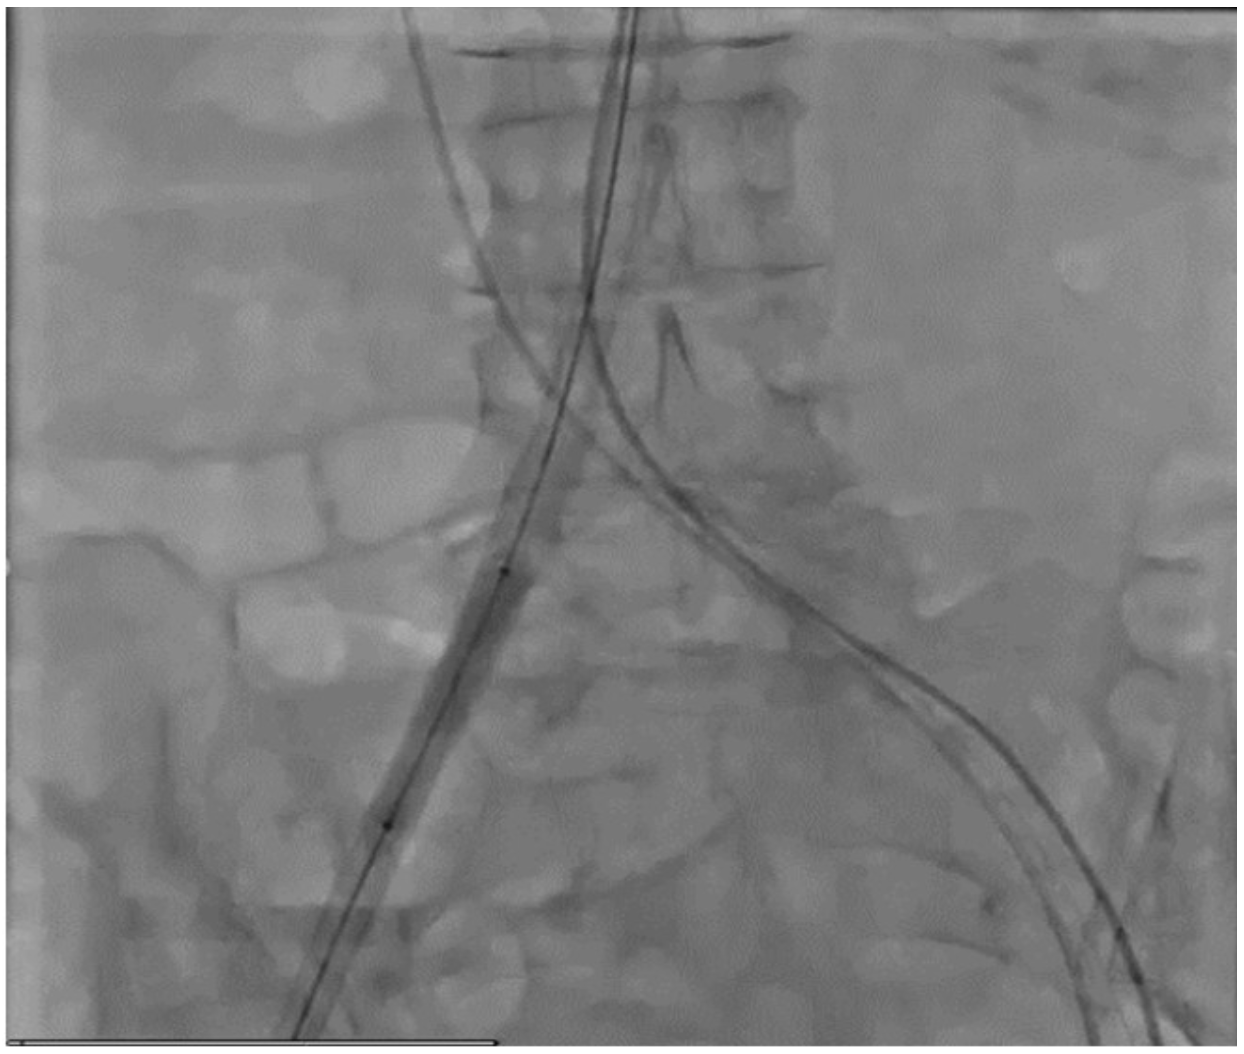

Steps in the procedure demonstrating simultaneous positioning of the Edwards Esheath the edwards esheath+ introducer set contains one introducer, one dilator, one expansion tool and a sheath,. A) an expandable sheath (esheath) (fig 1) that provides access into the target. the edwards sapien 3 transcatheter heart valve (thv), model 9600tfx, and accessories are indicated. the edwards esheath introducer set is intended for introduction of interventional devices into the. Edwards Esheath.